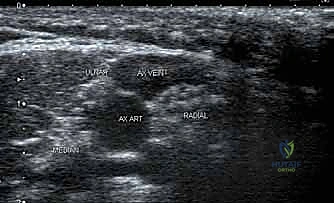

عندما يقرر الأستاذ الدكتور محمد هطيف بالتنسيق مع استشاري التخدير استخدام "التخدير الناحي" (Regional Anesthesia)، فإن الهدف يكون تعطيل إشارات الألم في هذه الضفيرة العضدية تحديداً قبل أن تصل إلى الدماغ. من خلال الفهم العميق لهذا التشريح ثلاثي الأبعاد، يمكن لطبيب التخدير استخدام أجهزة الموجات فوق الصوتية (السونار) لتحديد موقع العصب بدقة متناهية، وحقن الدواء المخدر حوله مباشرة.

الإحصار الإبطي (Axillary Block):

- الاستخدام: الخيار الأكثر أماناً وشيوعاً لجراحات الساعد، الرسغ، واليد (مثل جراحات تسليك العصب الأوسط، إصلاح أوتار اليد، كسور الرسغ).

- الموقع: يتم الحقن في منطقة الإبط حيث تتفرع الأعصاب حول الشريان الإبطي. يتميز بأنه بعيد تماماً عن الرئتين، مما يجعله آمناً جداً لمرضى الجهاز التنفسي.